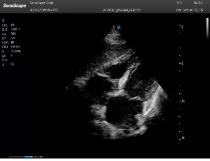

不同的探頭對應(yīng)于不同的臨床領(lǐng)域,不同的探頭頻率也應(yīng)用于不同的人體組織。超聲波在人體中的衰減與探頭頻率有關(guān),探頭頻率越高,穿透力越弱,分辨率越高,而探頭頻率越低,穿透力越強(qiáng),分辨率越低。因此在檢查淺表器官時應(yīng)選用高頻探頭,而檢查深部臟器時則選用穿透性強(qiáng)的低頻探頭。